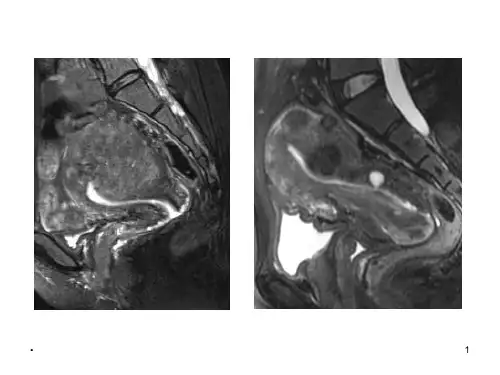

子宫结合带及腺肌症的MRI表现

MRI揭示子宫结合带及对腺肌症的诊断价值

【上图】了解子宫形态、位置无需烦恼,MRI会一目了然。